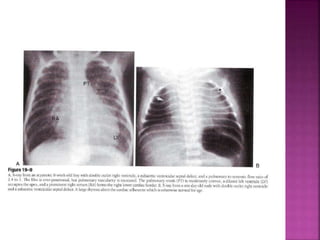

 ECHO

DELINEATE : sub pulmonary VSD , Over ride of

Pulm trunk over VSD, Absent PS, coexistence

of sub aortic stenosis, coarc Ao, and PDA

subpulmonary VSD

• size in relation to the diameter of the pulmonary artery

• presence and severity of a subpulmonary obstruction

• subcostal coronal and parasternal long axis planes

RV

PA

Guideline DORV